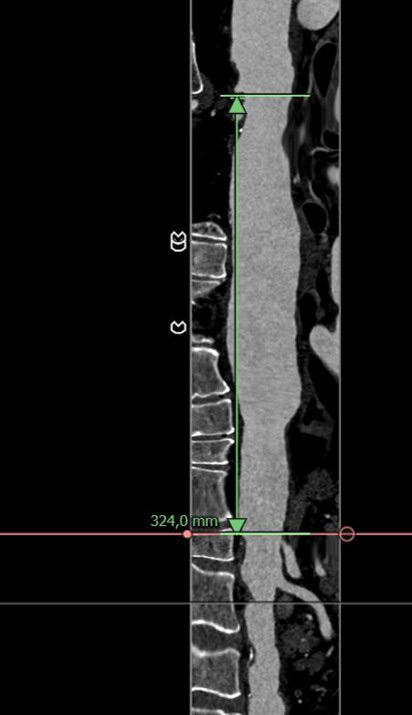

Distal Arch / Proximal descending

Length & extent

Distal landing zone